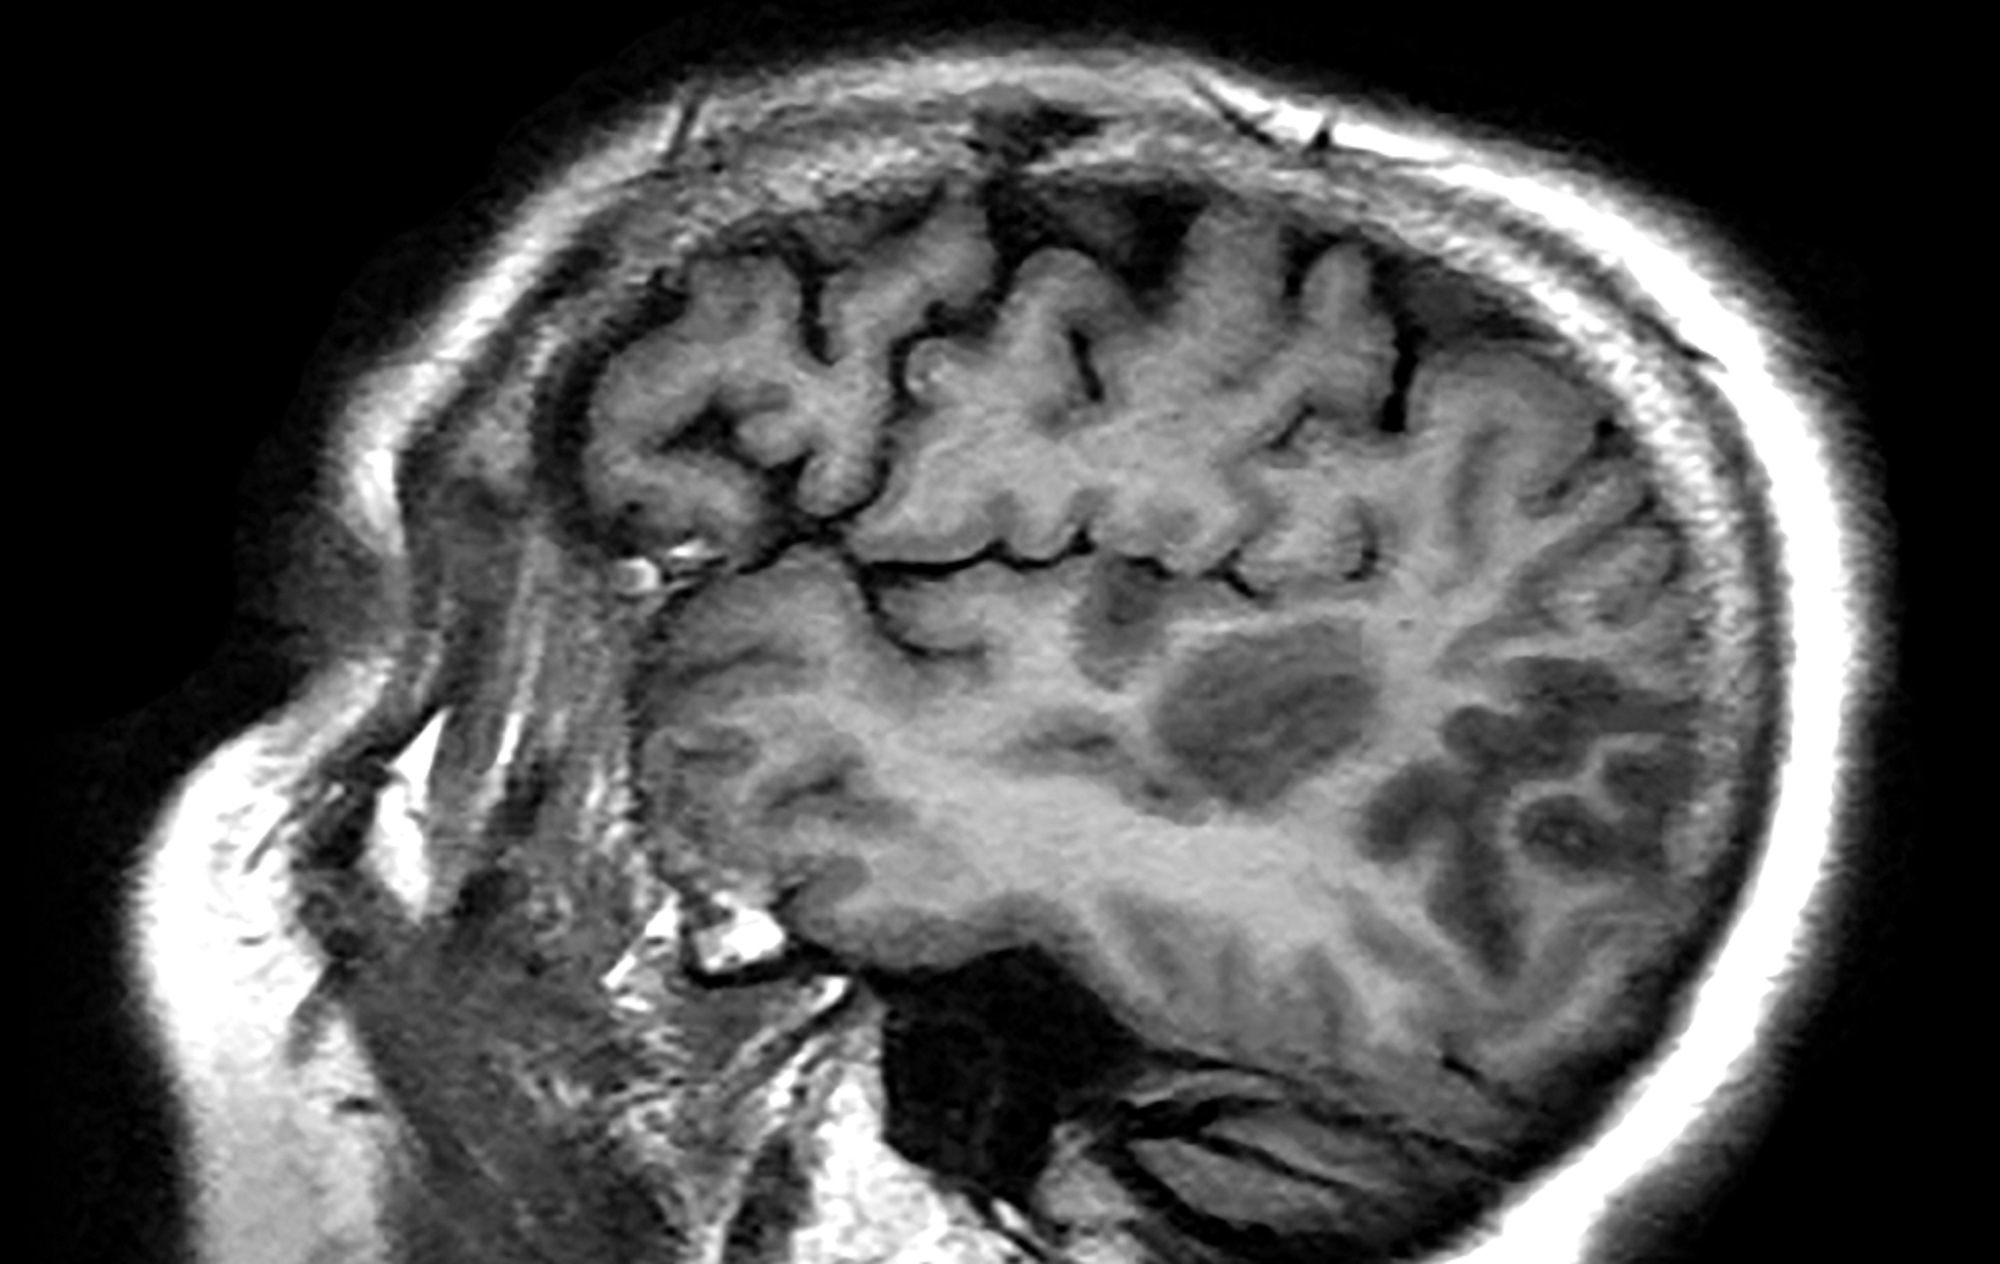

Other challenges relate to the use of diagnostic imaging. Computed tomography (CT) is preferred for detection of stroke in adults but CT has been reported to miss acute ischemic stroke in up to 47% of pediatric cases, and stroke mimics are difficult to distinguish on CT.8 Quick access magnetic resonance imaging (MRI) is much more useful in identifying strokes as well as many stroke mimics; however, access to this technology is often limited at healthcare centers that do not have a specific pediatric stroke protocol.9 The need for sedation in children to obtain the MRI presents special risks, and changes that occur in the brain during childhood development make MRIs more challenging to read.6 The possible presence of metallic orthodontia may also interfere with a clear MRI scan.6